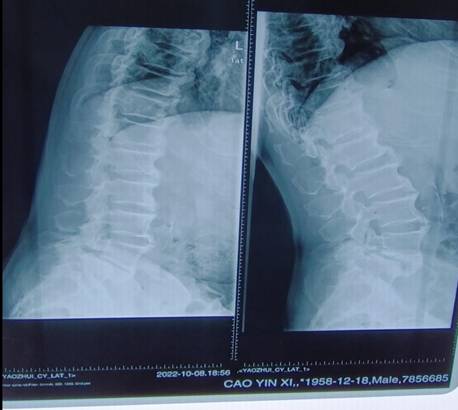

患者术前影像资料